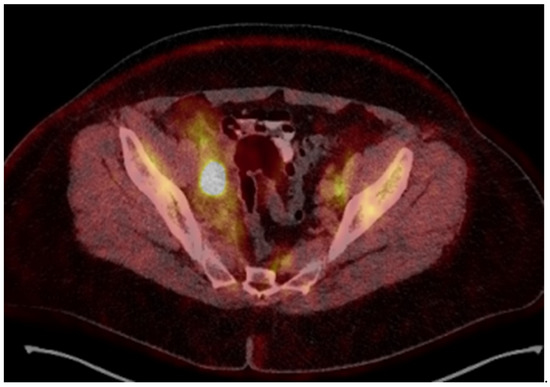

Figure 5.

Dose distribution: prescribed dose per fraction—7 Gy (red isoline)—covers more than 90% of the CTV high risk; 50% of the prescribed dose per fraction—3.5 Gy (blue isoline)—covers more than 99% of the CTV intermediate risk. The dose on the skin surface was 0 Gy from EBT.